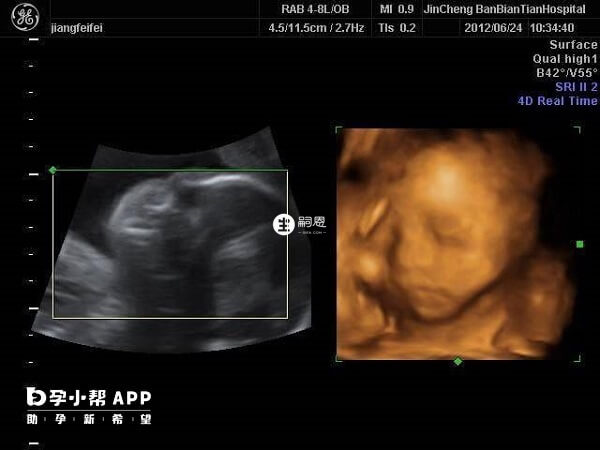

我剛剛懷孕6個月,這是我的二胎了。老大是個男孩子,所以我和老公決定給他生個妹妹。前幾天做四維檢查,通過檢查結果我和老公都很開心,因為顯示是個女孩子。但是我看網上還有人說,有許多人六個月的四維彩超到最後卻生出了男孩,所以想了解一下6個月的四維是女孩結果生了男孩的例項多嗎?6個月四維女孩卻生了男孩的例項還是有的,但是不是特別多。因為現在四維彩超的準確率很高,且懷孕6個月後基本胎兒的生殖器官已經發育好了,大部分情況下是不會出現誤判的。不過現在我國禁止提前告知胎兒性別,因此醫生一般會避開生殖器檢查,而四維彩超的資料來看胎兒性別是沒有科學依據的,因此如果懷孕6個月四維是女孩,但生下來是男孩的情況是存在的。

四維彩超可以清晰看見寶寶的狀態,是孕期胎兒排畸的重要檢查手段,懷孕6個月的四維準確率一般可以達到80%左右了,但還是有誤判的可能,一般是因為以下幾種原因: